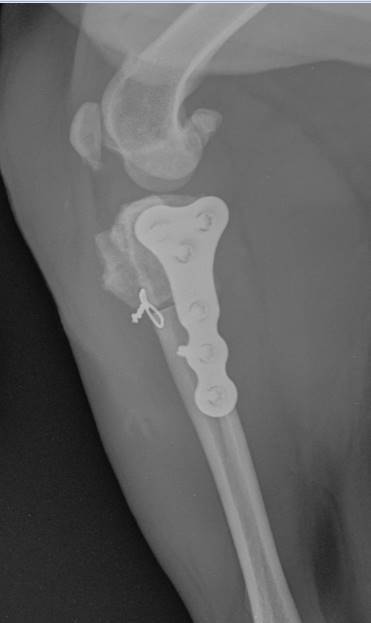

Cranial Closing Wedge Osteotomy (CCWO) is the universal surgery to manage canine cranial cruciate ligament disease. Suitable for dogs large and small, young and old it offers flexibility beyond any other tibial osteotomy technique.

• To understand the biomechanics of the cruciate ligament deficient stifle and cranial closing wedge osteotomy

• To understand pre-operative surgical planning and implant selection